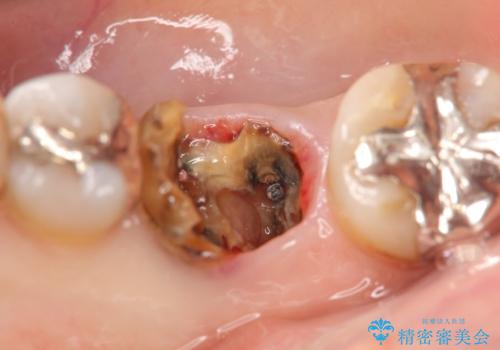

右下の銀歯(右下6)を除去したところ、虫歯が深く保存不可能な状態でした。

ブリッジ、インプラント、入れ歯の3つの選択肢を提案したところ、ブリッジをご希望されました。

抜歯後十分に歯肉の治癒を待ったのち、ブリッジによる補綴治療を行いました。